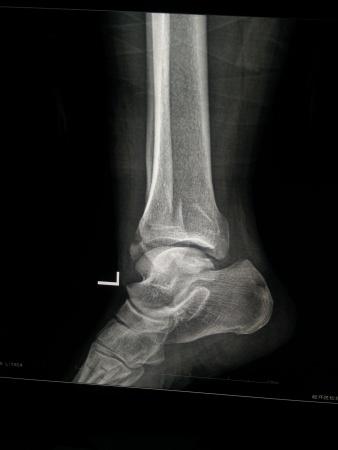

左三踝骨折手术治疗

患者女,外伤后左踝关节活动受限1小时入院,

入院后查体:左踝关节肿胀,活动受限,行DR及左踝关节CT检查,如下图,手术待肿胀消退后行手术治疗,目前愈合良好,请问问各位老师,好久可以下地呀, 下胫腓联合镙钉3个月取呀,

这个下胫腓螺钉真的没有必要打,另外后踝的两枚螺钉怪怪的,从后往前打的,看着钉子帽偏内侧,这个应该在外侧才对,